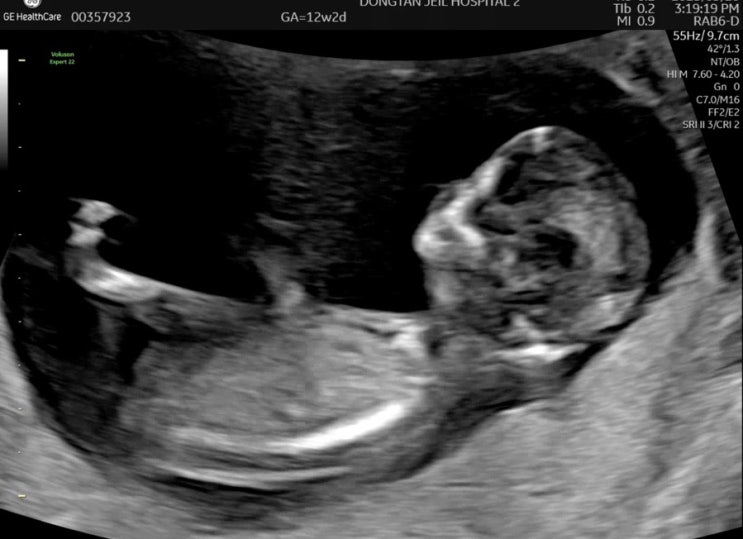

[임신12주차] 동탄제일병원 1차 기형아검사, 니프티 검사 (결과지 수령, 검사기간, 장꾸맘 성별)

12주차에 전원과 동시에 1차 기형아 검사 예약! 동탄제일병원이 워낙 예약이 어렵다고 해서 4주전에 미리 ...